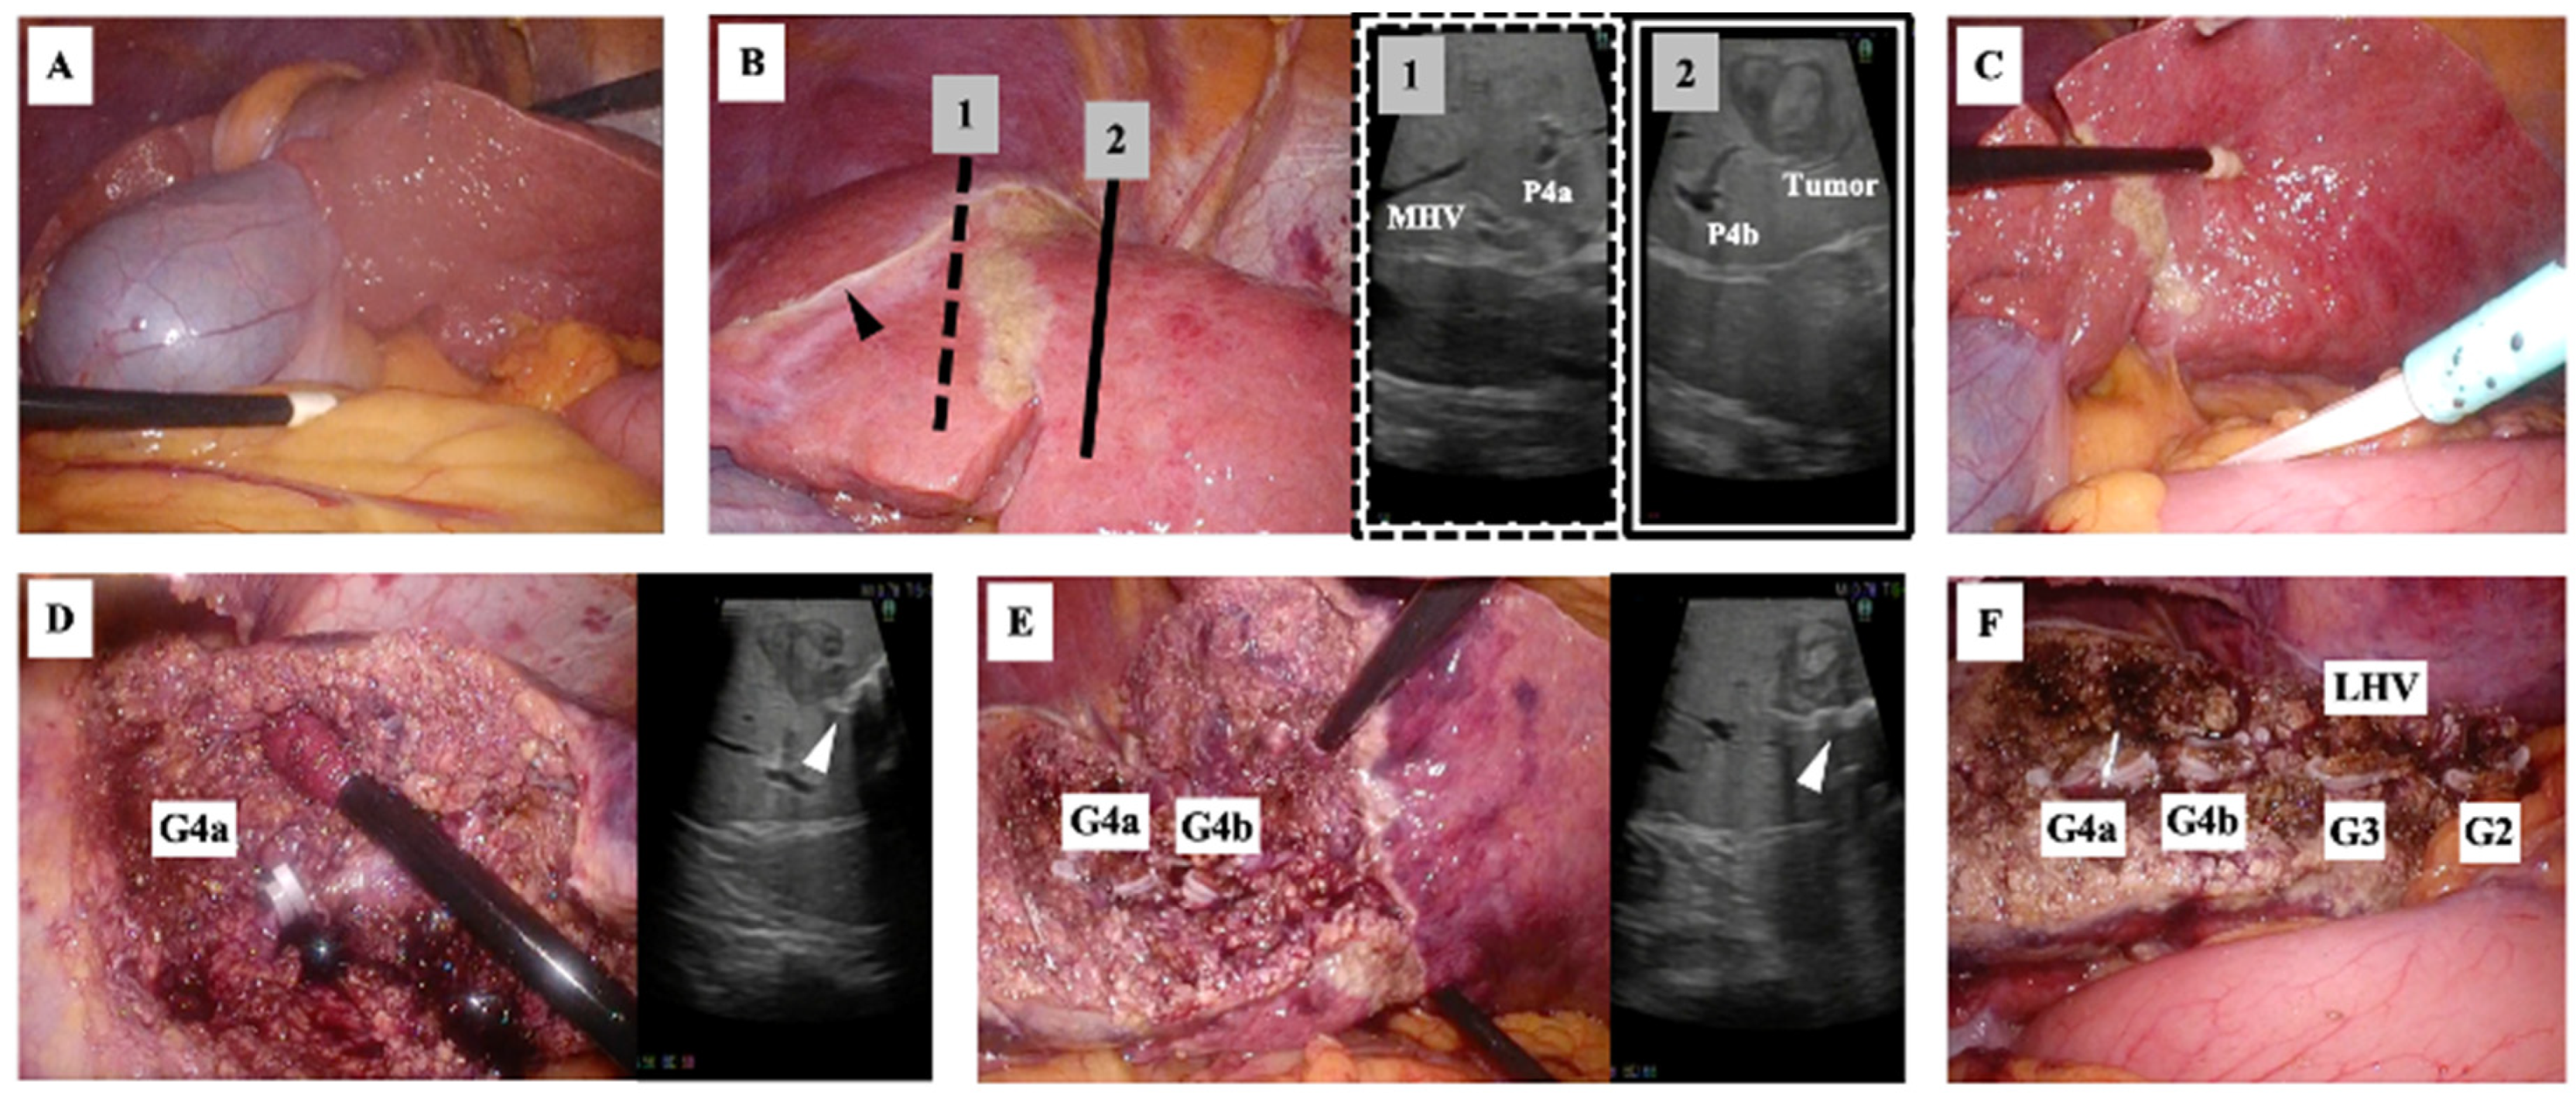

Surgery was performed with the patient in the supine position using a 2K high-definition/three-dimensional monitor. Five laparoscopy ports were placed: a 12 mm camera port at the umbilicus, 12 mm ports below the xiphoid process and below the right rib arch, and 5 mm ports outside the right and left rib arches. After confirmation of the RSLT and the location of the gallbladder (Figure 6A), the falciform ligament and left triangular ligament were dissected. The tumor was then located using ultrasonography. To determine the extent of resection while avoiding damage to the right-sided vasculature, the head side was marked at the boundary between S4b and the right anterior section (Figure 6B) and the caudal side was marked at the line where the S4a remained (Figure 6C). The liver resection was performed using a cavitational ultrasonic surgical aspirator (CUSA®︎ Excel; Integra, Princeton, NJ, USA) and ultrasonic scalpel (Harmonic®︎ HD 1000i shears; Ethicon, Raritan, NJ, USA). The medial inferior, medial superior, lateral inferior, and lateral superior branches of Glisson and left hepatic vein were individually double-clipped using a polymer locking ligation system (Hem-o-lok®; Teleflex, Wayne, PA, USA) and resected. Thin vein branches were clipped using a metallic clip applier (Endo Clip®; Medtronic, Dublin, Ireland) and cut. Finally, the left lateral section, including the partial left median section, was resected (Figure 6D, E, F). Operation time was 7 hours 35 minutes. Blood loss volume was 109 mL. The patient’s postoperative recovery was uneventful and he was discharged on postoperative day 7. The final pathological diagnosis was well-differentiated hepatocellular carcinoma.

Figure 6. Intraoperative photography. A) The ligamentum teres was positioned on the right and the gallbladder was on the left. B) After the locations of the tumor and middle hepatic vein (MHV) were confirmed using ultrasonography, the resection line was planned to avoid damaging the MHV. The hepatic attachments of the falciform ligament (black arrowhead) were located more to the right than normal. P4a and P4b indicate the medial inferior and medial superior branches of the portal vein, respectively. C) The planned resection line on the undersurface of the liver was marked. D and E) The extent and depth of resection (white arrowhead) were confirmed using ultrasonography. The medial inferior (G4a) and medial superior branches of Glisson (G4b) were clipped and cut. F) Resection of the liver parenchyma advanced in a left dorsal direction, clipping and cutting the lateral superior (G2) and lateral inferior branches of Glisson (G3) and the left hepatic vein. Finally, the left lateral section, including the partial left median section, was resected.